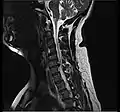

Cervical disc herniation

Herniated disc at C6–C7 level

Cervical disc herniations occur in the neck, most often between the fifth and sixth (C5–6) and the sixth and seventh (C6–7) cervical vertebral bodies. There is an increased susceptibility amongst older (60+) patients to herniations higher in the neck, especially at C3–4.[23] Symptoms of cervical herniations may be felt in the back of the skull, the neck, shoulder girdle, scapula, arm, and hand.[24] The nerves of the cervical plexus and brachial plexus can be affected.[25]